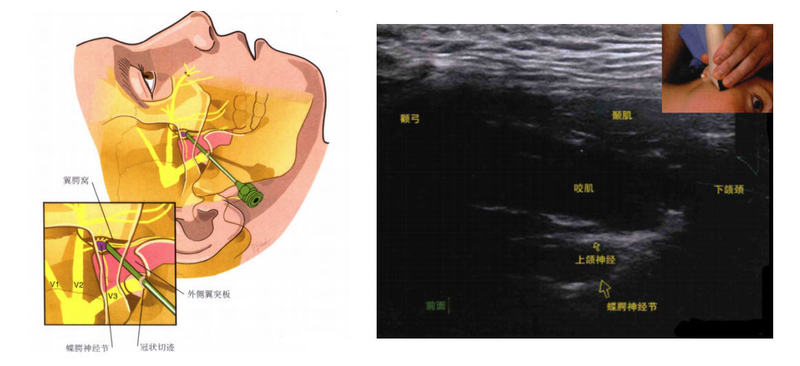

丛集性头痛(clusterheadache,CH)作为其中的一种亚型,临床表现为严格单侧眼眶、眶上和/或颞部的极重度疼痛,伴痛侧自主神经症状和(或)不安、躁动感,由于其发作时疼痛程度剧烈,又被称为“自杀性头痛”。CH易并发焦虑、抑郁和攻击性行为,并可能出现多种并发症(如心血管疾病和自杀倾向等),导致了CH的极大疾病负担。 LeoneM,CecchiniAP.Advancesintheunderstandingofclusterheadache[J].ExpertRevNeurother,2017,17(2):165-172.PetersenAS,LundN,SnoerA,etal.Theeconomicandpersonalburdenofclusterheadache:acontrolledcross-sectionalstudy[J].JHeadachePain,2022,23(1):58.对于药物治疗无效的难治性CH或对常规治疗不耐受时,可使用无创或有创的神经调控治疗,以减少头痛对于病人的严重不良影响以及致残性。由于蝶腭神经节相对容易接近,并且与副交感神经系统有关,因此被认为是具有治疗潜力的部位。尽管有近一个世纪的治疗兴趣,但临床数据很少,SPGB的最佳技术尚未确定。非侵入性阻断方法包括可卡因、酒精和利多卡因的鼻内应用,已经产生了有希望的结果。其他更具侵入性的技术,如射频消融和脉冲射频,已经产生了积极的结果。DevoghelJC.Clusterheadacheandsphenopalatineblock.ActaAnaesthesiolBelg.1980;32(1):101–7.KittrelleJP,GrouseDS,SeyboldME.Clusterheadache:localanestheticabortiveagents.ArchNeurol.1985;42(5):496–8.RobbinsL.Intranasallidocaineforclusterheadache.Headache:TheJournalofHeadandFacePain.1995;35(2):83–4.斯莱德于1909年对SPG进行了最早的干预。他使用浓度为4%、10%和20%的可卡因来消除现在被称为丛集性头痛的症状。SluderG.Theanatomicalandclinicalrelationsofthesphenopalatine(Meckel’s)gangliontothenoseanditsaccessorysinuses.ARElliottPublishingCompany;1909.Devoghel继续了Sluder的工作,并于1981年进行了迄今为止最大的SPGB研究。在这项研究中,通过颧上入路进入SPG,随后酒精渗入神经节。120名患者符合丛集性头痛的标准,其中103名患者(85.8%)与丛集性头疼相关的疼痛和副交感神经症状完全消失。Devoghel报告称,16名患者在1至2年内无疼痛,17名患者在2至3年内无痛苦,另有8名患者在3年或更长时间内无疼痛。DevoghelJC.Clusterheadacheandsphenopalatineblock.ActaAnaesthesiolBelg.1980;32(1):101–7.靶向蝶腭神经节的最简单方法是自我引入一种涂有可卡因或利多卡因的棉头鼻内涂抹器。当使用鼻内可卡因治疗时,Barre研究的11名患者中有11名报告头痛强度降低了65%以上。BarreF.Cocaineasanabortiveagentinclusterheadache.Headache:TheJournalofHeadandFacePain.1982;22(2):69–73.11名患者中有10名报告称,在2分钟和30秒内,其丛集性头痛的强度降低了80%。Kittrelle随后进行的一项规模较小的研究显示,经鼻滴注利多卡因的结果相似。KittrelleJP,GrouseDS,SeyboldME.Clusterheadache:localanestheticabortiveagents.ArchNeurol.1985;42(5):496–8.在Kittrelle的研究中,五名患者中的四名报告称,在施用4%利多卡因液滴后的3分钟内,他们的头痛强度降低了75%或更大。对利多卡因溶液无反应的独居患者对5%可卡因溶液也无反应。罗宾斯在30名患者中报告了类似的成功,其中4%利多卡因鼻喷雾剂被用治疗。RobbinsL.Intranasallidocaineforclusterheadache.Headache:TheJournalofHeadandFacePain.1995;35(2):83–4.早期双盲安慰剂对照试验,Costa等人试图比较10%盐酸可卡因溶液和10%利多卡因溶液对硝酸甘油引起的丛集性头痛患者疼痛的成功率。这项研究包括15名患者,100%的患者报告硝酸甘油引起的头痛疼痛缓解,两种麻醉剂的疗效相似。与前面提到的研究不同,科斯塔和他的团队在前鼻镜检查的指导下双侧给药。科斯塔认为,棉签应用和液滴给药可能不准确,鼻腔阻塞可能会限制目标部位的进入或吸收。因此,前鼻镜引导的SPGB被认为是一种更准确的给药方法。Costa认为,前鼻镜技术的使用归因于其集群性头痛的高成功率。CostaA,PucciE,AntonaciF,SancesG,GranellaF,BroichG,NappiG.Theeffectofintranasalcocaineandlidocaineonnitroglycerin-inducedattacksinclusterheadache.Cephalalgia.2000;20(2):85–91.据报道,使用局部麻醉剂和皮质类固醇混合物的内镜技术存在差异。FelisatiG,ArnoneF,LozzaP,LeoneM,CuroneM,BussoneG.Sphenopalatineendoscopicganglionblock:arevisionofatraditionaltechniqueforclusterheadache.Laryngoscope.2006;116(8):1447–50.由于这些方法更具侵入性,风险更大,内镜方法可能最适合于治疗慢性丛集性头痛患者,这些患者难以接受药物干预。锥形束计算机断层扫描(CBCT)已被证明是先前研究中使用的荧光透视模式的有效替代[24]。CBCT使用数百个平面投影图像渲染近实时三维射线图像。与传统的计算机断层扫描相比,这提高了解剖可视化和针放置的准确性,减少了对辐射的暴露。LoombaV,UpadhyayA,KaveeshvarH.Radiofrequencyablationofthesphenopalatineganglionusingconebeamcomputedtomographyforintractableclusterheadache.PainPhysician.2016;19:E1093–6.RFA的另一种选择是脉冲射频(PRF)。与射频消融不同,脉冲射频是一种非破坏性、非消融性的技术,利用射频能量的爆发来产生疼痛缓解。虽然确切的机制尚不清楚,但PRF的止痛特性被认为是独立于热消融发生的,相反,它与持续射频消融过程中未发现的蛋白质表达变化有关。HiguchiY,NasholdBS,SluijterM,CosmanE,PearlsteinRD.ExposureofthedorsalrootganglioninratstopulsedradiofrequencycurrentsactivatesdorsalhornlaminaIandIIneurons.Neurosurgery-Baltimore.2002;50(4):850–6.Chua等人向SPG进行了第一个记录在案的PRF病例系列。本研究中有三名患者有丛集性头痛病史。两名患者在4个月内无症状,而第三名患者仅经历了部分疼痛缓解。尽管这项研究的结果得出了褒贬不一的评价,但它首次证明PRF可以作为对保守疗法无反应的患者的可接受替代方案ChuaNH,VissersKC,Wilder-SmithOH.Quantitativesensorytestingmaypredictresponsetosphenopalatineganglionpulsedradiofrequencytreatmentinclusterheadaches:acaseseries.Painpractice.2011;11(5):439–45.